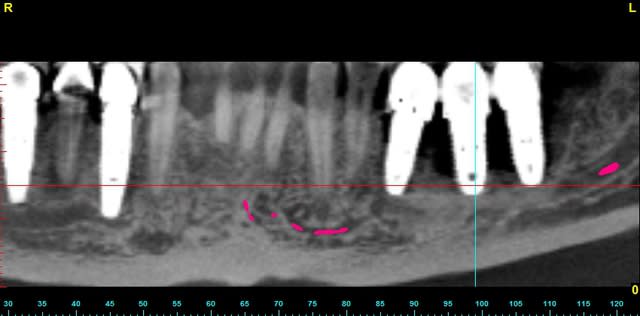

quelques images en 3 D...

Bernard overview edbft1 - Eugenol

Bernard overview  2  nlgyly - Eugenol

Bernard panoramic l8hei0 - Eugenol